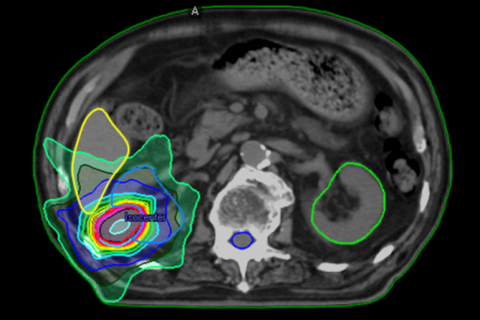

前立腺がんに対するDWA照射

治療の精度と低侵襲の両立を重視した前立腺がん放射線治療の提供

これらはいずれも、麻酔をして体内に器具を入れる処置を伴う治療方法です。

当院では、治療装置に内蔵された CBCT(コーンビームCT)装置を用いて、治療直前に前立腺周囲の画像を撮影し、臓器の位置を確認しています。 このため、体内に金マーカーを埋め込むことなく、前立腺の位置を確認・補正しながら、安全で精度の高い放射線治療を行うことが可能です。加えて、2023年に治療計画を作成する専用のコンピュータを更新し、DWA(Dynamic Wave Arc)による治療が可能となりました。これにより、以前よりもさらに前立腺に放射線を集中させながら、直腸への線量を効果的に抑える線量分布を作成できるようになりました。そのため、体内にハイドロゲルスペーサーを注入する処置を行わなくても、安全性に配慮した放射線治療が可能となっています。これにより、金マーカーやハイドロゲルスペーサーを体内に入れるという処置の侵襲を避けながら、安全性と治療精度の両立を図っています。